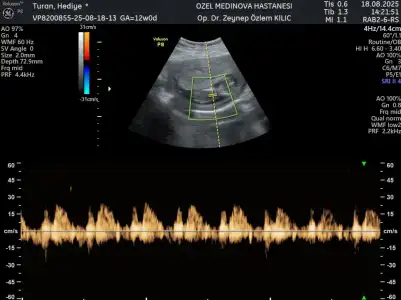

Merhaba arkadaşlar Sizce cinsiyet nedir 12 haftalık iken . İkili tarama için özele gittim doktor bir yorumda bulundu 15 haftalık kendi kendi doktoruma gittim o da bir yorumda bulundu ama ben sizin düşüncelerinizi merak ediyorum iki doktorun da kız yönünde tahmin yaptı ama kesin bir şey demediler ilk 2 fotoğraf 15 haftalık öbürü de 12